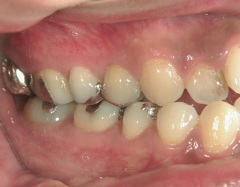

矯正歯科 治療後矯正歯科 全顎ワイヤー矯正 治療後矯正歯科(全顎ワイヤー矯正)治療後

全顎ワイヤー矯正 症例(18)

30歳女性 浜松市北区在住

治療期間3年4ヶ月

主訴:前歯の歯並びが気になる。

矯正歯科 治療前 上顎を装置(QH)で拡大後ワイヤー矯正へ移行、右下5番左下4番 計2本抜歯叢生改善

矯正歯科 治療後